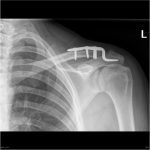

Can You Heal an AC Joint Dislocation Without Surgery? Exploring Non-Surgical Options